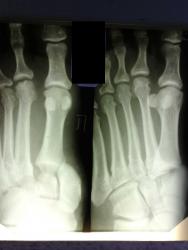

Я позволил себе нeмного обработать снимок; я указал стрелкой "смутивший" меня участок кортекса, мне кажется что целостность кортикальной пластинки нарушена, кортекс как бы отслоен по типу козырька. При таких картинках вызывающие сомнения; мы всегда говорим с травматологами; если у пациента болей в данной точке нет, значит и перелома нет. )))

Марио, это наружный край суставной пов-ти основания 5 пл. кости, именно этот край, вернее его захождение на наружный край суст. пов-ти кубовидной кости, является маркером подвывиха плюсны.

А в основание 5ой пястной кости, есть нарушение целостности кортекса с "козырьком", вероятно перелом?

Это край суставной пов-ти.

Женщина подвернула ногу (обувь с высоким каблуком).